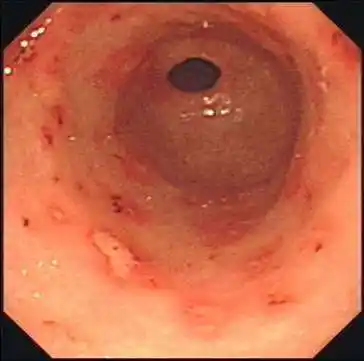

图3 慢性胃炎在胃镜检查时的"花斑"样表现(与图2正常比较观看)